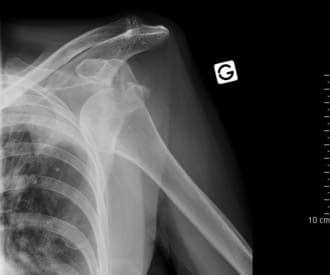

Clinically, dislocations at the shoulder are described by where the humeral head lies in relation to the glenoid fossa. Anterior dislocations are the most prevalent (95%), although posterior (4%) and inferior (1%) dislocations can sometimes occur. Superior displacement of the humeral head is generally prevented by the coraco-acromial arch.

An anterior dislocation is usually caused by excessive extension and lateral rotation of the humerus. The humeral head is forced anteriorly and inferiorly – into the weakest part of the joint capsule. Tearing of the joint capsule is associated with an increased risk of future dislocations. Hill-Sachs lesions (impaction fracture of posterolateral humeral head against anteroinferior glenoid) and Bankart lesions (detachment of antero-inferior labrum with or without an avulsion fracture) can also occur following anterior dislocation.

Fig 1.4 - Anterior dislocation of the shoulder joint.

Fig 5

Anterior dislocation of the shoulder joint.